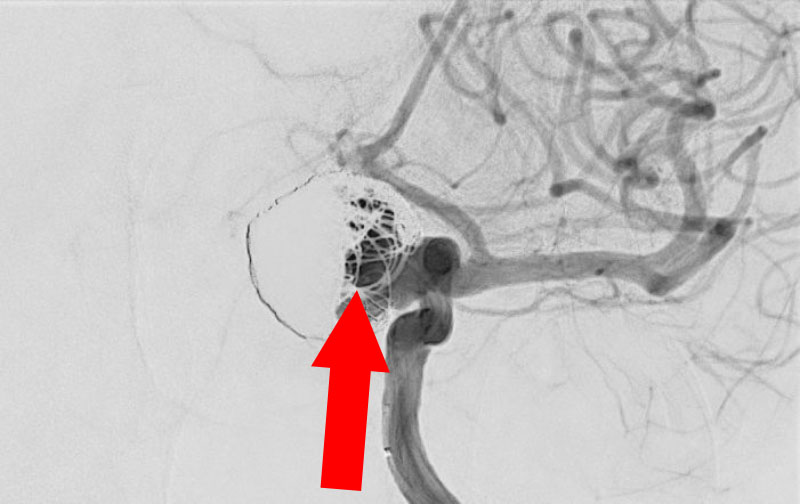

No.1631 手術前